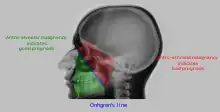

| Maxillary sinusitis[2] | ![]() Differentiating pathology in maxillary sinus

| Polyp |

| Malignancy |

![]() Onhgren's line